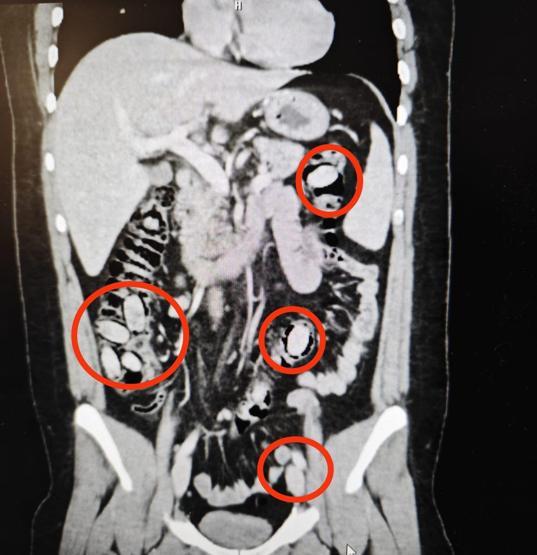

Eskişehir'de polisin şüphe üzerine durdurduğu S.A.’nın (25) midesinde 44 kapsül uyuşturucu bonzai maddesi olduğu tespit edildi. Hastanede cerrahi müdahaleyle kapsüller çıkarılırken, şüpheli erkek S.A. tutuklandı.

Eskişehir Emniyet Müdürlüğü ekipleri, yurtdışından Eskişehir’e geldiği belirlenen S.A.’yı kent girişinde durdurdu. Sürekli midesini tutmasından şüphe edilmesi üzerine S.A., hastanede sağlık kontrolünden geçirildi.

Şüpheli S.A.’nın hastanede çekilen röntgeninde midesinde 44 kapsül olduğu tespit edildi. Eskişehir Cumhuriyet Başsavcılığı’nın talimatıyla cerrahi müdahaleye alınan S.A.’nın midesindeki 44 kapsül çıkarıldı.

Kapsüllerde yapılan incelemede içerisinde uyuşturucu metamfetamin (bonzai) maddesi olduğu belirlendi.

Hastanede tedavisi tamamlanan S.A., taburcu edilirken, polis ekiplerince gözaltına alındı. İşlemlerinin ardından adliyeye sevk edildn S.A., ‘uyuşturucu ticareti’ suçlamasıyla tutuklanarak cezaevine konuldu.